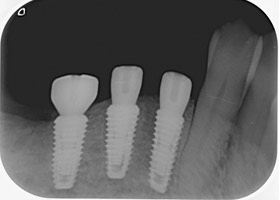

分別植牙後X光片

植牙後癒合狀況良好